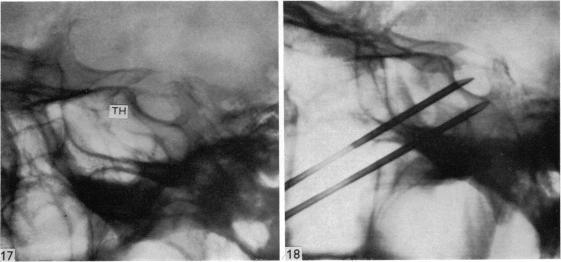

Surgical aspects of the anatomy of the sphenoidal sinuses and the sella turcica.

J Anat. 1977 Dec;124(Pt 3):541-53.